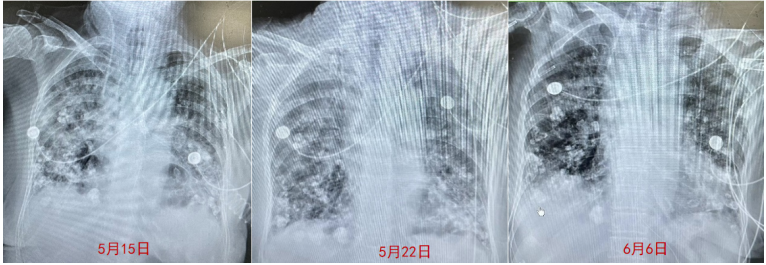

5月12日床旁胸片示患者两肺纹理增多、增粗、模糊,两肺多发斑片模糊影,较5月11日胸片明显进展图5。使用多黏菌素后体温未降,胸片示病变继续进展,激素加量至80 mg q12h。5月12日血气分析提示氧合指数为71 mmHg。与患者及家属沟通后行气管插管有创机械通气(先后予A/C-VC模式、A/C-PC模式、PRVC模式)。5月15日甲泼尼龙加量至160 mg。患者体温变化如图6所示。

图片

图5  患者5月11日和12日胸片变化比较

5月25日呼吸机模式调整为PSV模式,同时肺康复训练。6月3日甲泼尼龙减量至40 mg。6月5日患者通过自主呼吸试验(SBT),拔除气管插管,双通道鼻导管吸氧-BiPAP(晚)序贯呼吸支持。6月6日复查胸部X线片见病变较前明显好转(图9)

图9  患者胸部X线片变化情况